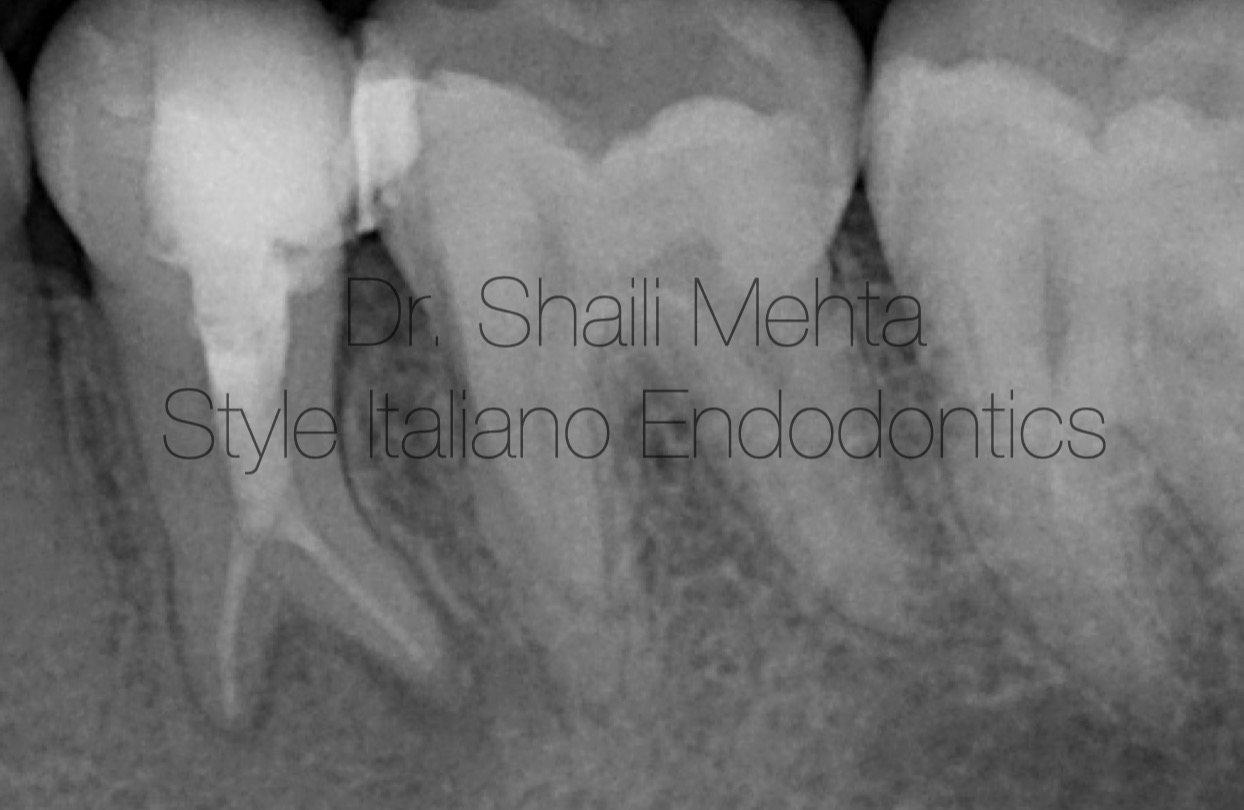

Fig. 3

Instrumentation utilized nickel-titanium rotary files (buccal: size 30/.04; lingual: size 30/.04). Copious irrigation with heated 5.25% sodium hypochlorite (NaOCl) was enhanced by Passive Ultrasonic Irrigation (PUI) for three cycles per canal to maximize biofilm disruption. Following final rinse protocols (17% EDTA and saline), the canals were medicated with non-setting calcium hydroxide paste for one week. At the second appointment, the patient was asymptomatic. Mastercone radiograph was taken.